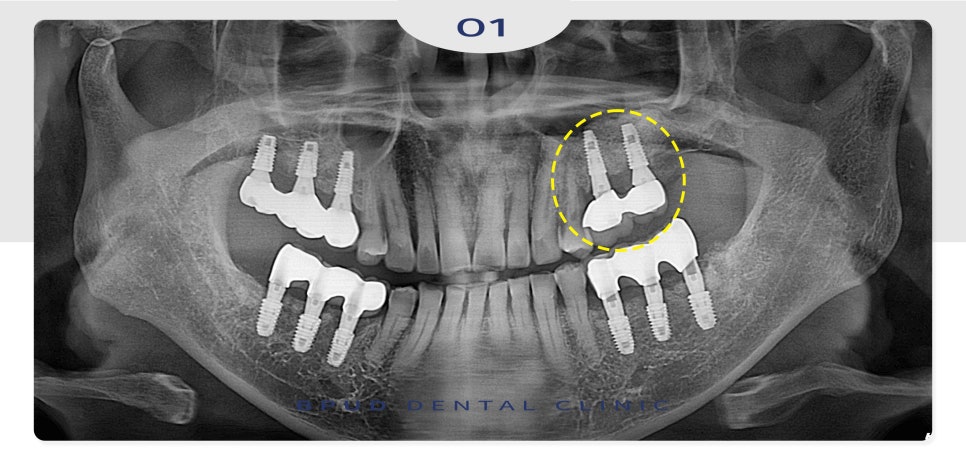

환자분께서는 처음 내원 당시

아래쪽의 치아들이 많이 흔들리고

상태가 좋지 않아 치료 상담을 위해

내원을 해주셨는데요.

처음 내원 당시부터 위쪽 임플란트가

좋지 않음을 설명드리고 주기적인

경과 관찰이 필요하다고 말씀을 드렸는데요.

그러나 오랜 기간 방치로 인해

약 2년 후, 주변에 뼈가 심각하게 소실되어

결국 상악동 내부로 임플란트가 빠져버린 채로

재내원해 주셨습니다.